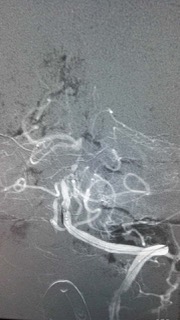

术中见患者基底动脉上段闭塞,典型的基底动脉尖综合征。基底动脉尖综合征是一种潜在的致命性神经系统疾病,进展极快,临床医生诊断和治疗该病面临很大挑战,其约占所有缺血性卒中的 1%-4%,死亡率更是高达75%。

术中结果不容乐观,如果基底动脉闭塞不处理,患者随时可能出现中枢性呼吸循环衰竭导致死亡。

目前最适合的救治办法是短时间内取出血栓,方能恢复脑血管血供,恢复患者神经功能。

脑动脉机械取栓术听起来简单,但操作起来难度颇大。其操作方法是:股动脉穿刺置入一根细细的导管,缓慢上行至脑血管,精确定位后再次置入一个取栓导丝,释放导丝,让导丝包裹血栓,再像拔红酒瓶塞一样回收导丝,取出血栓。

手术要求的精细度极高,对操作者的技术水平、熟练程度、心理素质、团队协作等都是极大的考验。江顺福主任都是有着多年血管介入临床经验的介入专家,血管内技术炉火纯青;吴明超副主任医师则刚刚从南京学了脑动脉取栓技术回到神经内科,对脑梗塞的治疗相当娴熟。两位专家充分运用纯熟的血管介入技术,密切配合,终于顺利取出了盘居在脑动脉内的“夺命血块”。经过1个多小时的紧张手术后,成功取出栓子,患者闭塞的基底动脉开通,术后安返病房严密监测及术后的继续治疗。术后24小时患者神志转清,能回答问题,家属非常感动。